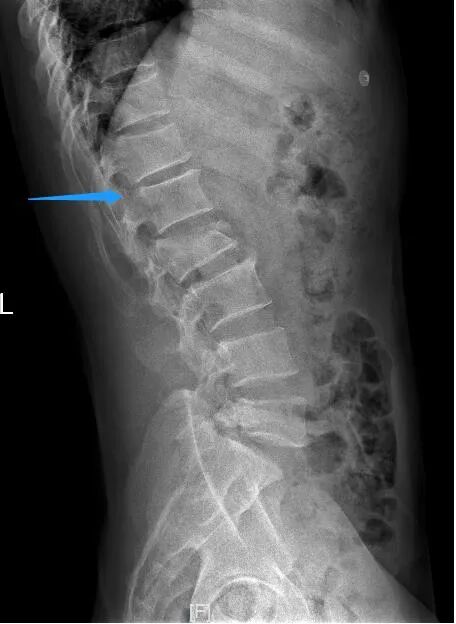

手术后当天,姚某右下肢已可轻微活动,经过1月余的专科康复后,姚某已可拄拐下地站立。他激动地说,“我以为自己将永远躺在床上了,想不到医生还能让我站起来,非常感谢医护人员高超技术和精心照顾。” 腰椎术前X线侧位片 术前磁共振 术前磁共振显示神经明显受压 姚某术后恢复情况 薛厚军副主任医师指出,脊柱骨折是临床常见脊柱损伤,发病群体是青壮年,指的是因外力对脊柱骨质造成连续性的破坏、高处坠落、车祸等高能量损伤是导致脊柱骨折的主要原因。对于严重的脊柱爆裂性骨折,可以造成脊髓或神经的损伤,导致肢体运动感觉障碍或者瘫痪,严重影响病人的生存及生活质量。所以,只要条件允许,应尽早手术治疗。 随着科技的进步以及人们自我保护意识的提高,近年来脊柱骨折的病人已有所减少,但对于其引起的严重后果我们仍不能忽视。建议广大民众出现脊柱骨折后要就近在有实力的医院诊治,搬动要严格轴线平抬,避免二次伤害,以免延误病情。